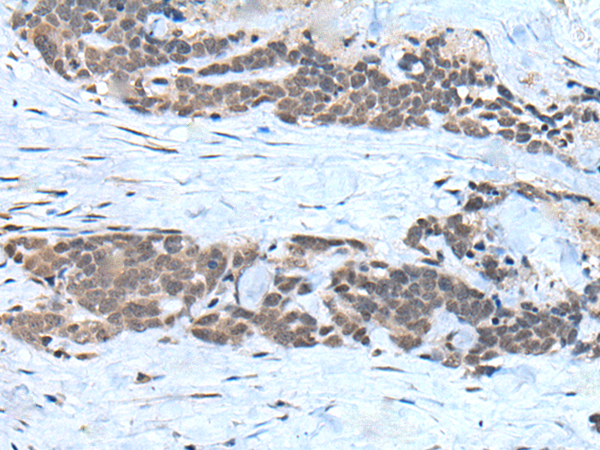

分类: 科研抗体货号: P09304别名: CIR1; UEV1; CROC1; UBE2V; UEV-1; UEV1A; CROC-1应用: WB,IHC反应种属: Human, Mouse